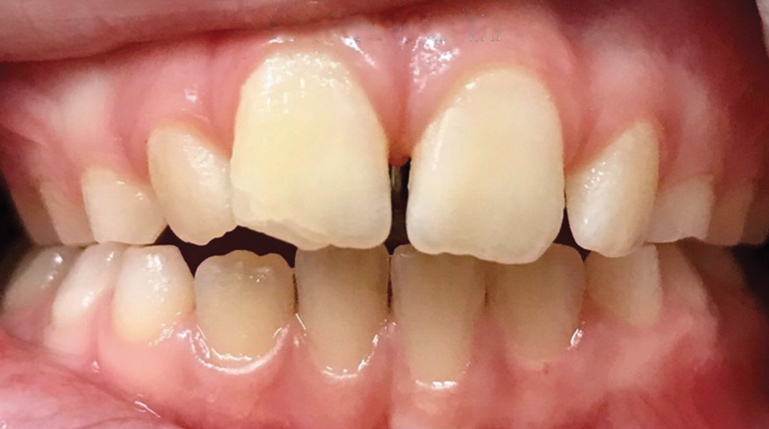

A common developmental abnormality is a localized anterior crossbite on permanent incisors, which may lead to trauma to these teeth. The most common cause of localized incisor crossbite is an anterior occlusal interference, which causes a functional shift when the patient moves from centric relation to centric occlusion (Figure 1 and Figure 2). This is not a true class III malocclusion, and proper diagnosis is critical to select the correct treatment. Sometimes this bite relationship is called a pseudo-class III relationship.2 Intervention in these cases is important because these teeth are at higher risk for recession, periodontal damage, and incisal chipping. Limited anterior braces and sometimes a palatal expander may be used to place the maxillary incisors facial to the mandibular incisors; this is referred to as "jumping the bite."

Fig 1. Functional shift in centric occlusion.

Figure 1

Fig 2. Functional shift in centric relation.

Figure 2